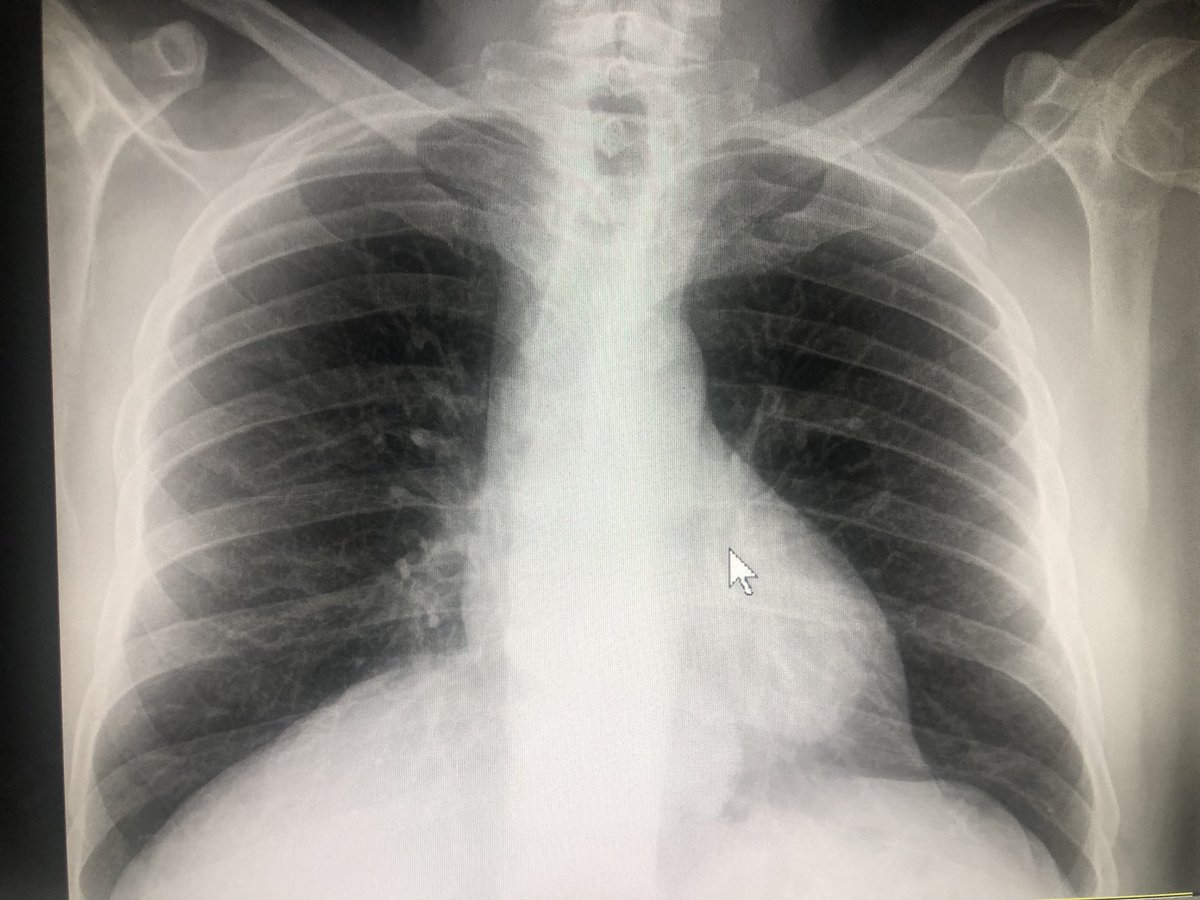

Pacient de 56 anys, hipertens. Al 2n dia de febre i tos, radiografia neta. Covid Positiu. 5 dies despres, pneumònia bilateral, i distrés respiratori. Contagi en entorn familiar. No és cap broma. #COVID19 #salut #Lleida

oyuguero's tweet image. Pacient de 56 anys, hipertens. Al 2n      dia de febre i tos, radiografia neta. Covid Positiu. 5 dies despres, pneumònia bilateral, i distrés respiratori. Contagi en entorn familiar. No és cap broma. #COVID19 #salut #Lleida